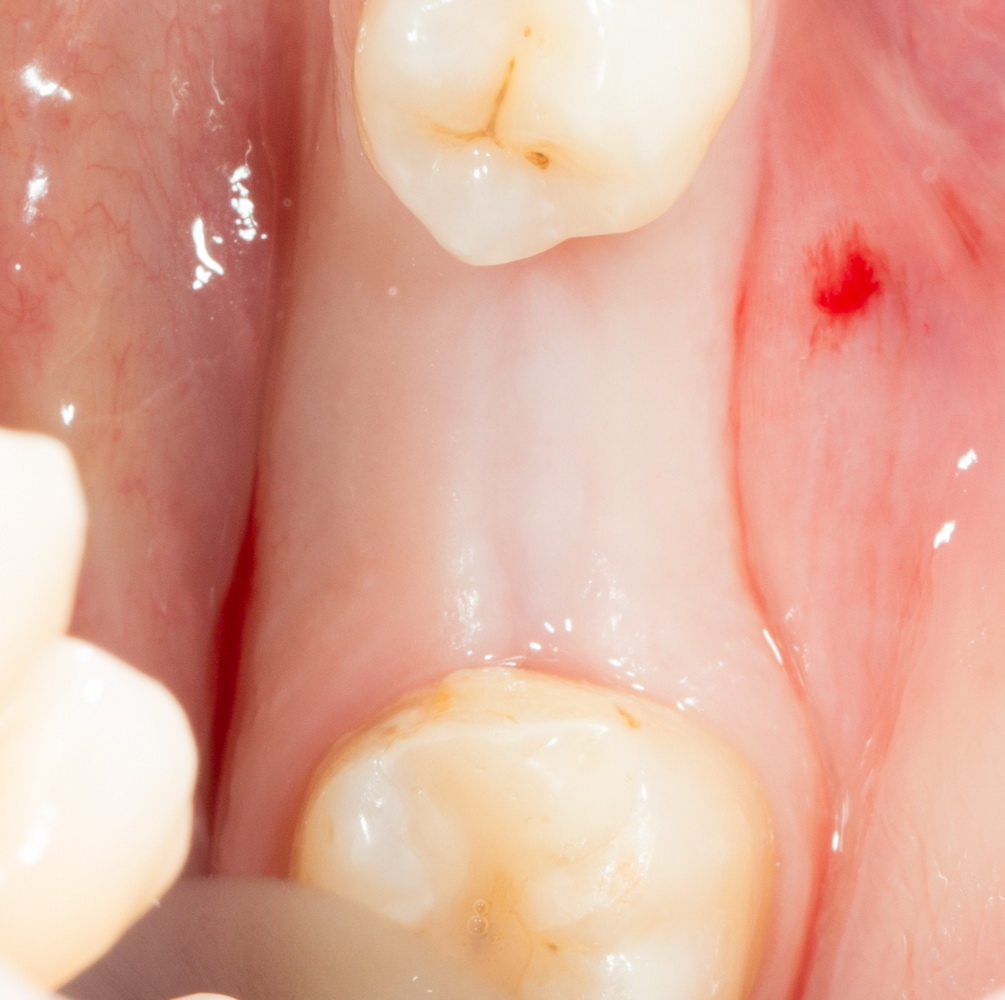

Другой способ понижения травматичности — это, по возможности, объединение нескольких этапов хирургического лечения в одну операцию. Типичный пример — немедленная имплантация: удаление зуба, установка импланта и формирование десны проводятся за один этап:

Можно существенно снизить травматичность хирургического вмешательства, просто уменьшив размер операционной раны. Для этого делается доступ точно по диаметру импланта. Такой подход называют «имплантацией без разрезов», что в корне неверно:

Чем меньше размер послеоперационной раны — тем меньше риски возникновения послеоперационных проблем и неудачного исхода. Однако, такой малоинвазивный подход не должен снижать качество и точность хирургического вмешательства. Несмотря на кажущуюся простоту, подобные операции сложнее и ответственнее, чем имплантация обычным доступом.